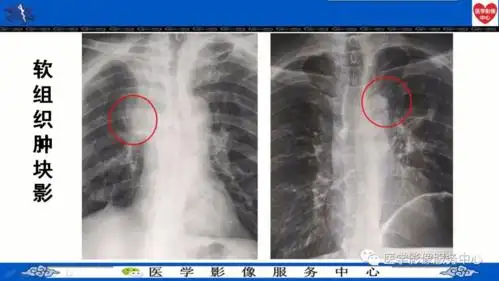

基础学习中央型肺癌典型征象